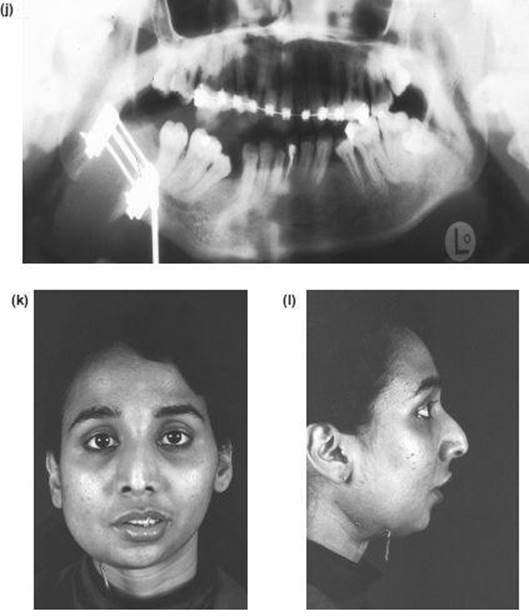

7. The nasal septum and pterygoid plates are separated intraorally, as in the Le Fort I operation.